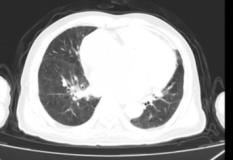

3月1日复查CT提示心脏增大;双肺多发少许磨玻璃影,不除外炎症吸收(图2-7-15)。

图2-7-15 2020年3月1日胸部CT